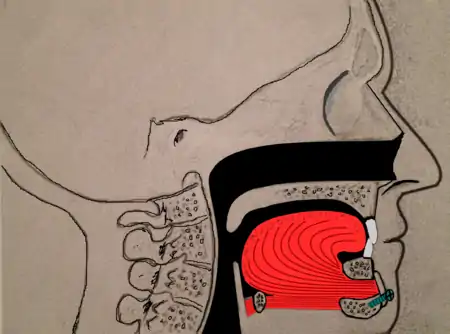

Maxillomandibular advancement

Maxillomandibular advancement (MMA) or orthognathic surgery, also sometimes called bimaxillary advancement (bi-max), or maxillomandibular osteotomy (MMO), is a procedure that moves the upper jaw (maxilla) and the lower jaw (mandible) forward. The procedure was first used to correct deformities of the facial skeleton, including malocclusion. In the late 1970s, advancement of the lower jaw (mandibular advancement) improved sleepiness in three patients. Subsequently, maxillomandibular advancement was used for patients with obstructive sleep apnea.

Currently, surgeons often perform maxillomandibular advancement surgery simultaneously with genioglossus advancement (tongue advancement). The genioglossus advancement pulls the tongue forward to decrease the amount of tongue blockage during sleep. MMA is one of the most effective surgical treatments for sleep apnea, with a high success rate. Nonetheless, the procedure is often used after other forms of treatment have failed (nasal surgeries, tonsillectomy, uvulopalatopharyngoplasty, tongue reduction surgeries). There is a longer recovery when compared to other sleep apnea surgeries, since the bones of the face have to heal into their new position.[9]